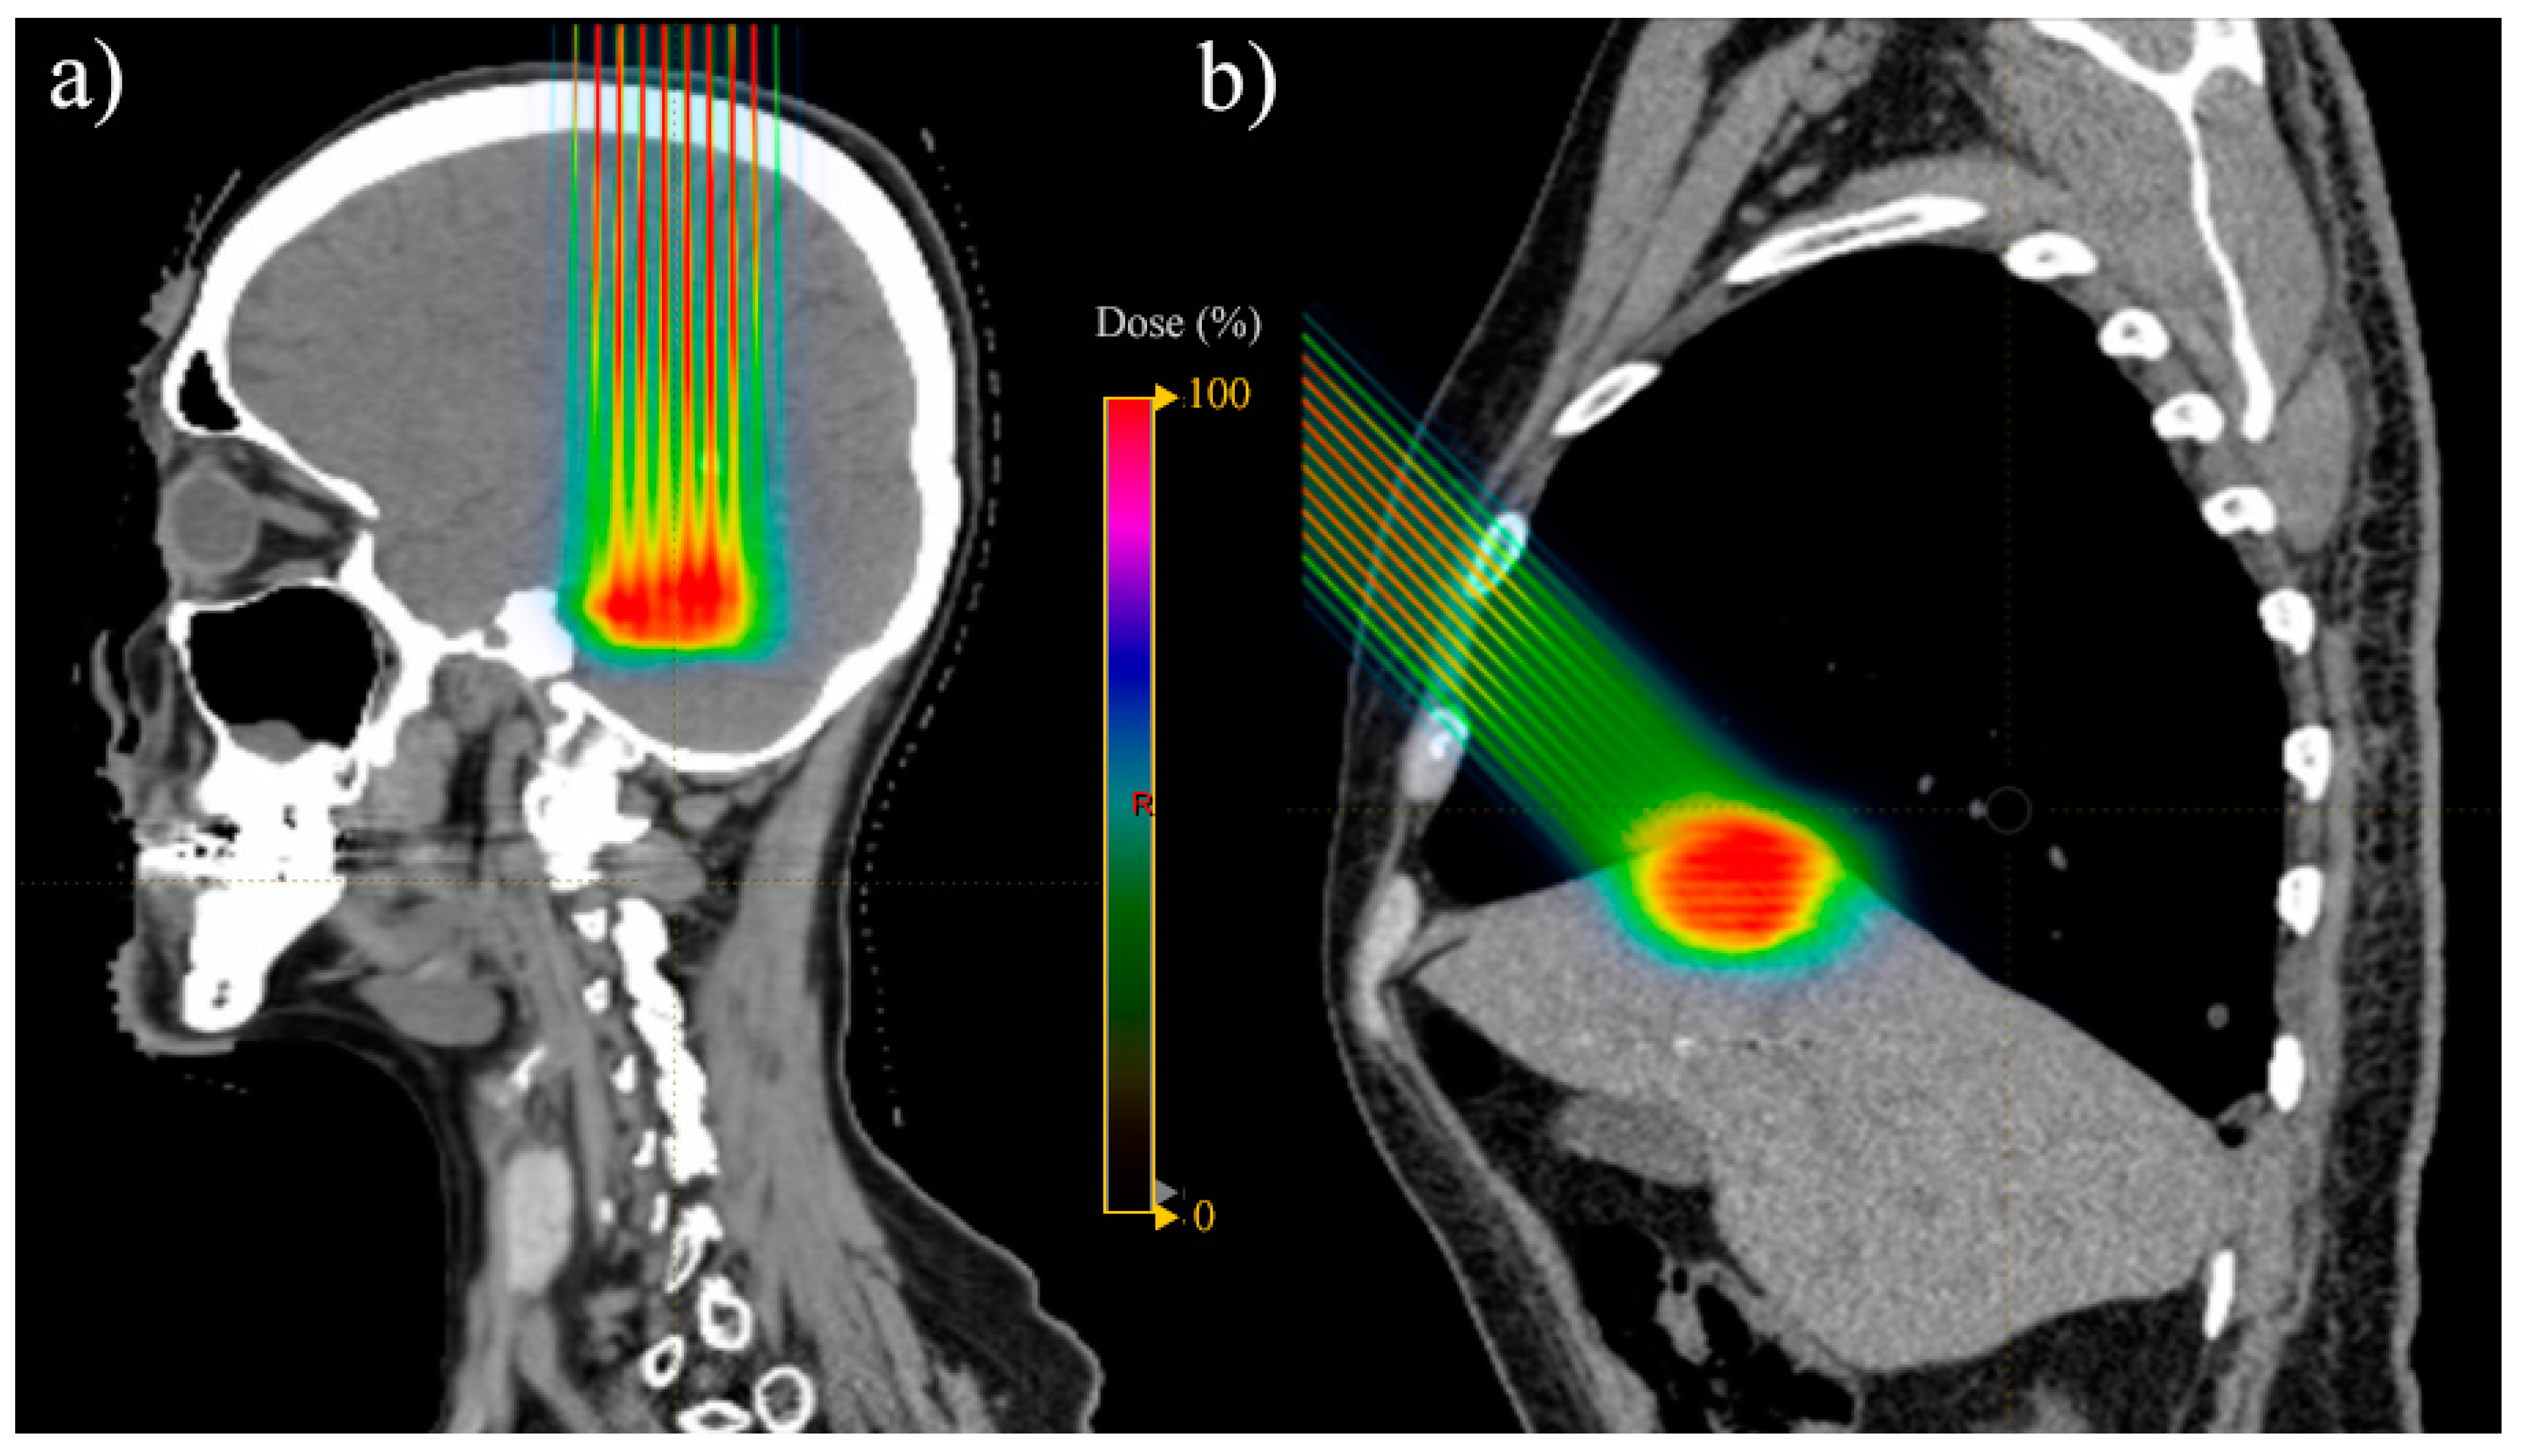

- Chang, S.; Liu, G.; Zhao, L.; Zheng, W.; Yan, D.; Chen, P.; Li, X.; Yang, K.; Deraniyagala, R.; Stevens, C.; et al. Redefine the Role of Spot-Scanning Proton Beam Therapy for the Single Brain Metastasis Stereotactic Radiosurgery. Front. Oncol. 2022, 12, 804036. [Google Scholar] [CrossRef] [PubMed]